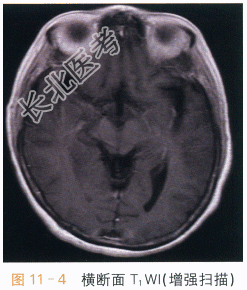

- [材料题] 患者,女,65岁,发热1周,伴神志异常2天。实验室检查:潘氏实验阳性,脑脊液白细胞计数升高,脑脊液蛋白升高。抗巨细胞病毒IgG阳性,抗单细胞病毒1型IgG阳性,抗EB病毒衣壳抗原IgG阳性。影像学资料及分析影像学资料如图11-1~图11-4所示。